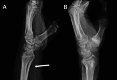

Wrist fractures and dislocations are frequently encountered in the emergency department and can cause significant long-term disability. Imaging plays a crucial role in the evaluation of wrist injuries, with conventional radiography being the first imaging investigation. Cross-sectional imaging is playing an increasingly important role in management of wrist injuries. Computed tomography with 3D and multiplanar reformatting capabilities is in particular useful for detailed evaluation of bony injuries and can provide vital information to orthopaedic surgeons for adequate surgical planning. In this article, we provide a brief review of the normal wrist anatomy, imaging appearance, and various patterns of fractures and dislocations commonly encountered in the emergency department.